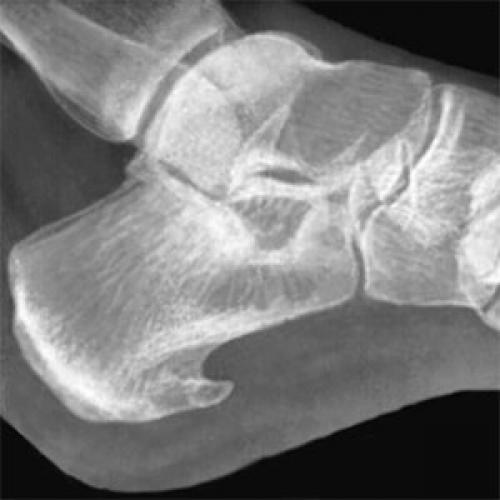

Это заболевание называется плантарный фасциит, или пяточная шпора. Такие симптомы до 7% взрослых испытывают. Суть заболевания в воспалении плантарной фасции (сухожилия, которое является рессорой стопы и помогает нам амортизировать свой вес при каждом шаге) в месте её прикрепления к пяточной кости. Как следствие плантарного фасциита в этом месте на пяточной кости образуется вырост в виде шипа, который и называют пяточной шпорой.